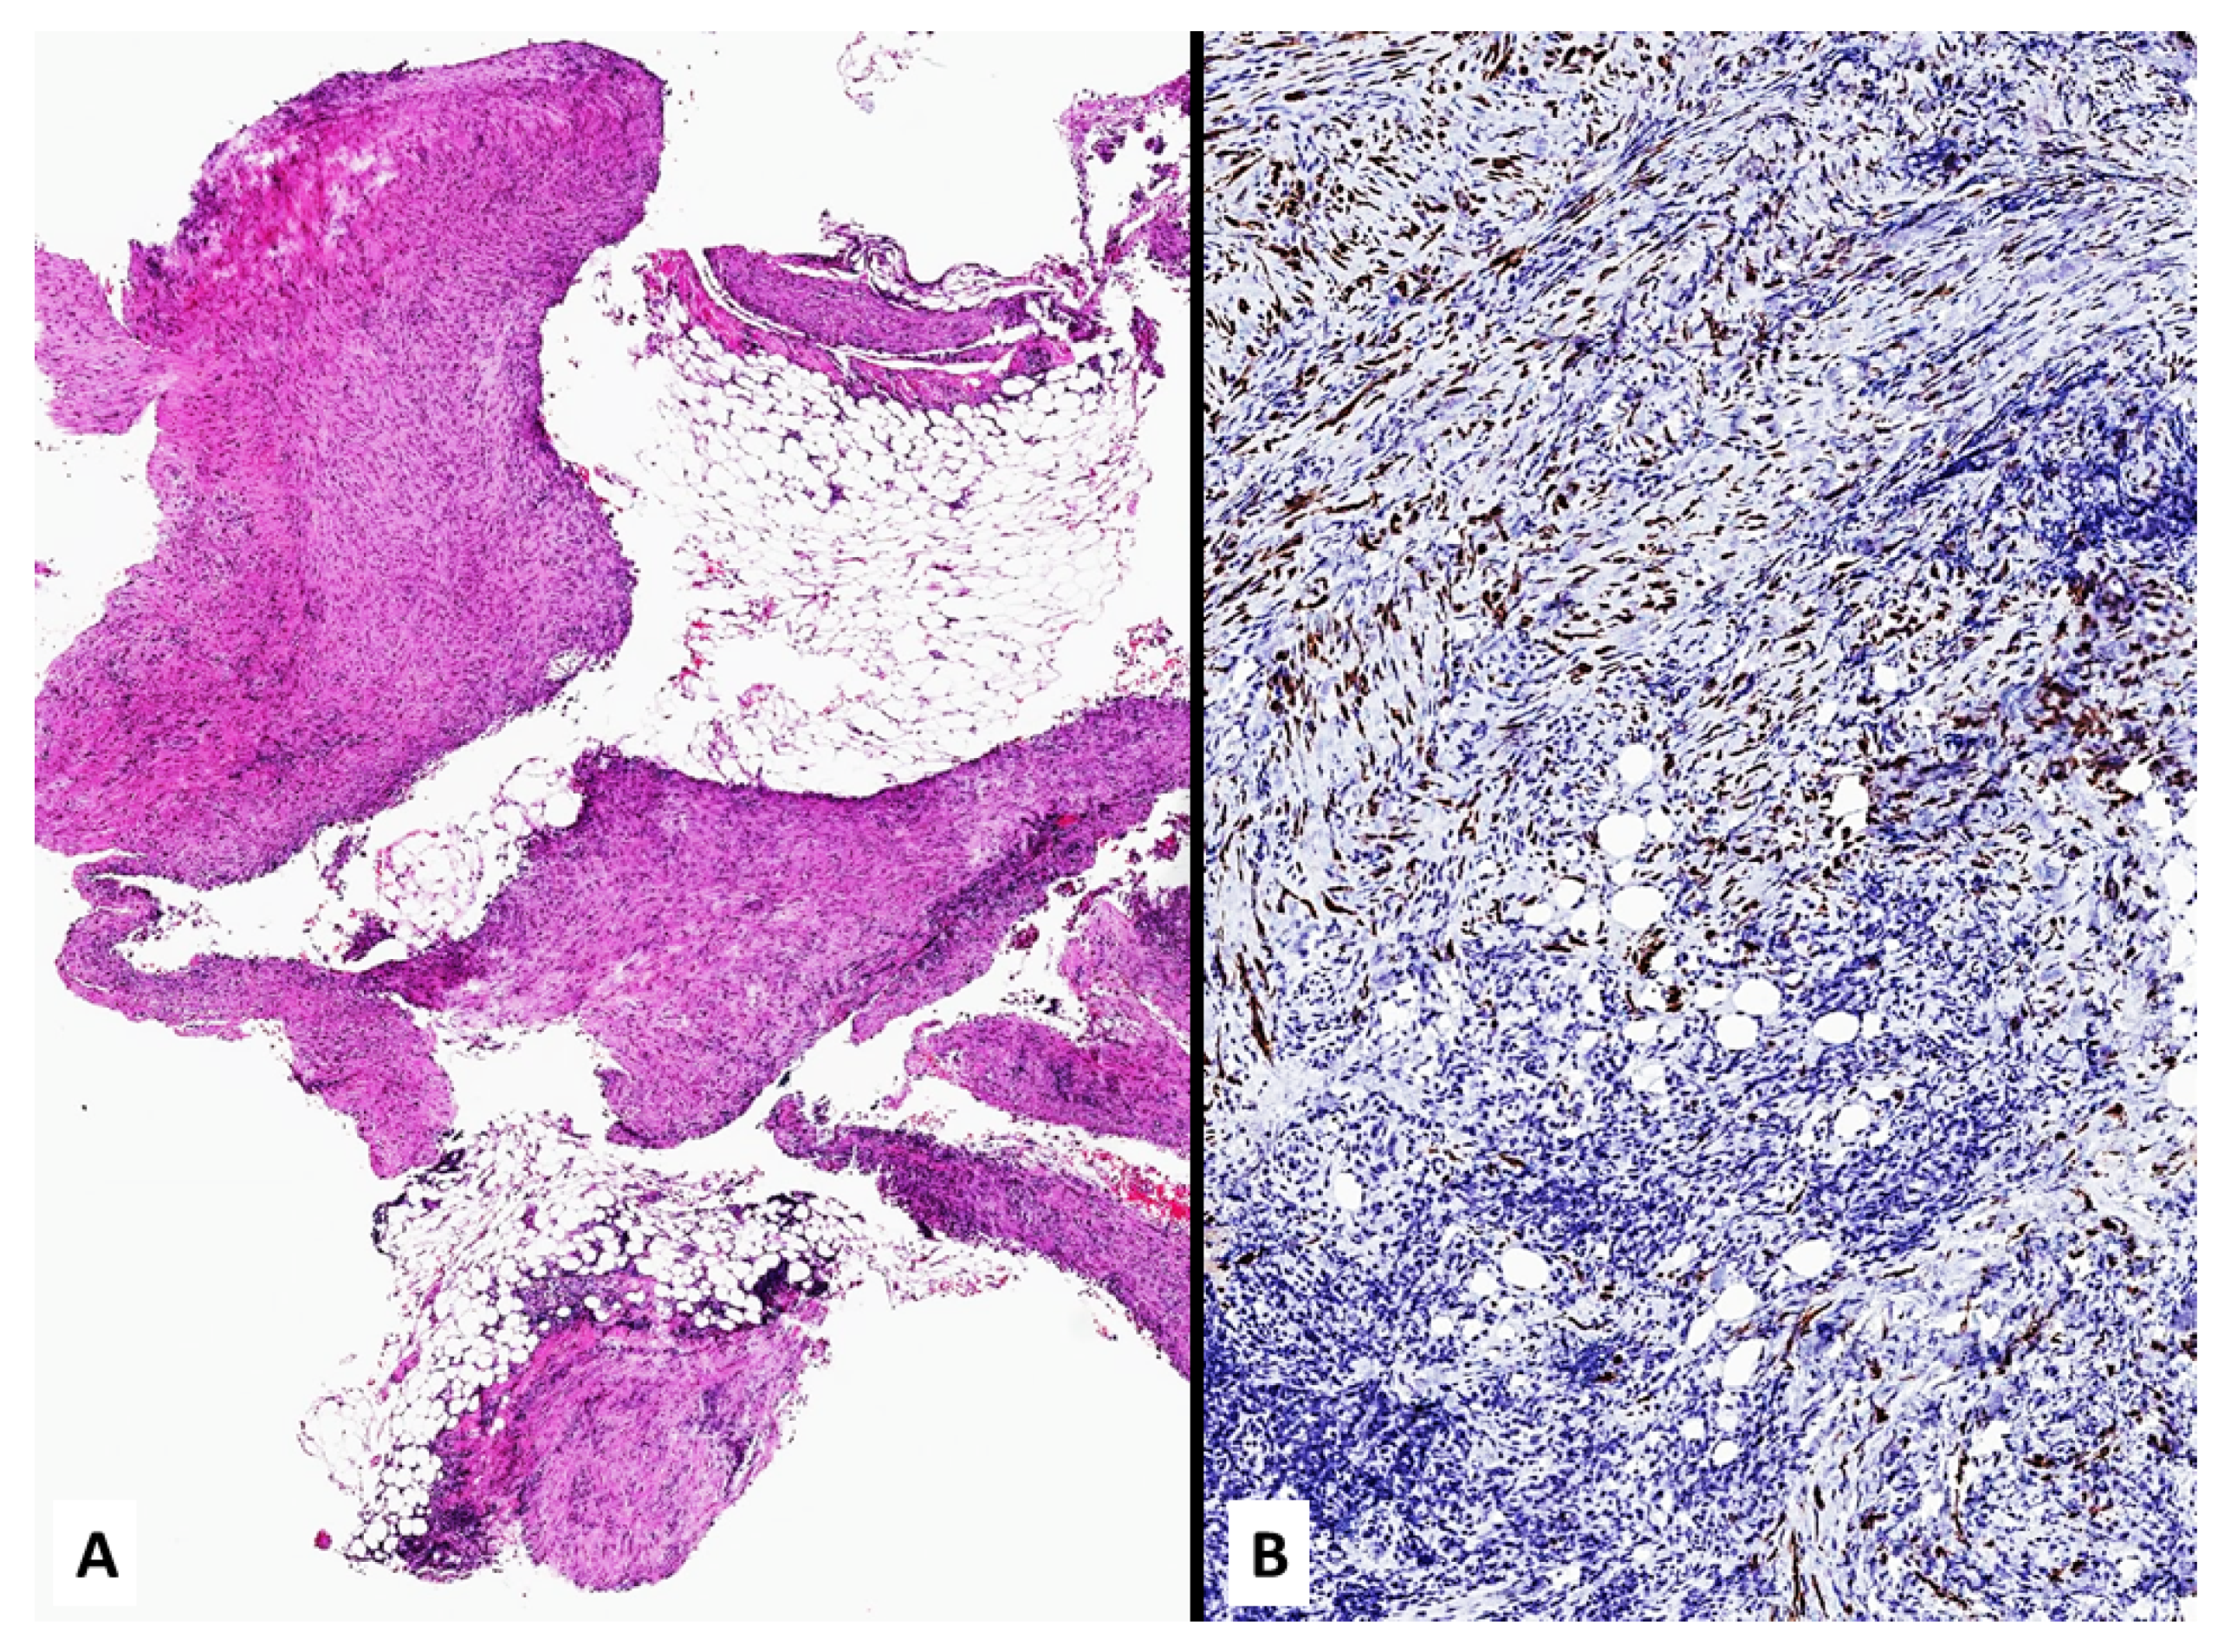

4. Unusual Morphologic and Immunohistochemical Features